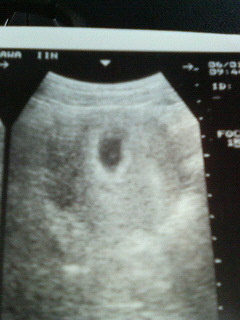

お腹からの超音波でした♪6週目だそうです。

心拍も確認できて安心しました。